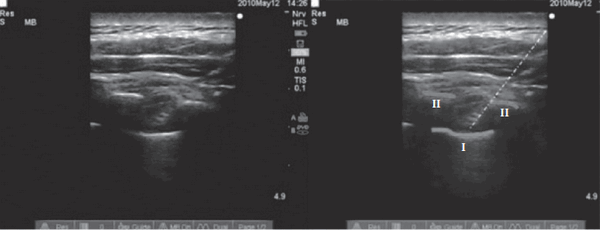

Рис. 4. УЗ-картина при проведении торакальной ПВБ (линия I — париетальная плевра,

линии II — очертание поперечного отростка, белая линия — паравертебральный катетер)

Medical Ultrasonography 2010; 12 (3): 223—227